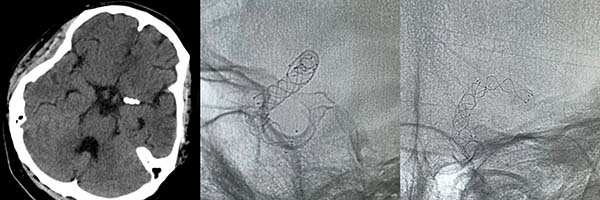

▲DSA显示

左侧颈内动脉眼动脉段血泡样动脉瘤,直径约1mm

神经外科脑血管病介入团队采取微创治疗,于载瘤动脉内套叠释放两枚编织支架,起到血流导向作用,部分阻断了进入动脉瘤的血流,降低了再出血风险。术后入住ICU,予机械通气,镇静镇痛、防治脑血管痉挛、脱水等治疗。定期复查头颅CT未再出血,无脑梗死及脑积水。患者病情逐渐好转,1个月后转至当地康复医院继续治疗。出院时患者神志清楚,可进食,混合性失语,左侧肢体不完全偏瘫。

▲术后影像可见套叠支架,动脉瘤处网孔密度较高

出院1个月后,神经外科团队对患者进行随访,患者语言及左侧肢体障碍已基本恢复。出院后2个月于当地医院复查脑血管造影,显示血泡样动脉瘤已完全闭塞,载瘤动脉通畅。家属对清华大学附属垂杨柳医院神经外科团队的及时救治表示万分感谢。目前患者正在为硕士研究生的新学期做准备。

▲术后3个月复查造影显示动脉瘤闭塞,载瘤动脉通畅